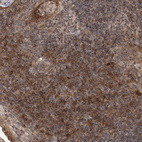

Immunohistochemical staining of human kidney, placenta, rectum and tonsil using Anti-DARS2 antibody HPA026506 (A) shows similar protein distribution across tissues to independent antibody HPA026528 (B).